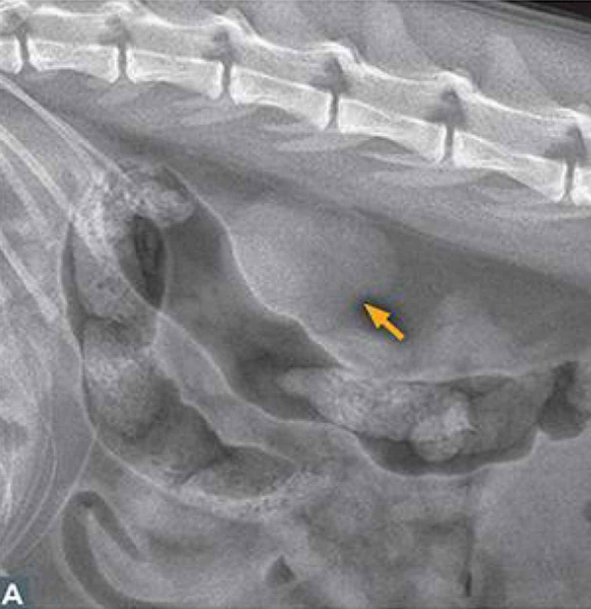

Imaging

- 칼슘이 과도하게 빠져나가는 이상이

- 전체적으로 뼈 밀도 감소 양상

- 영구 조직 mineralization

- 초음파만으로는 1/2기 구분 어려움